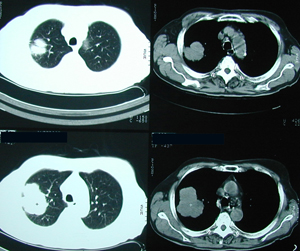

Figure 3

Chest CT scan that confirms the chest X-ray findings. It shows a lobulated tumour-mass located in the right lung.